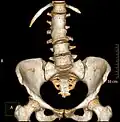

Block vertebrae

Block vertebrae occur when there is improper segmentation of the vertebrae, leading to parts of or the entire vertebrae being fused. The adjacent vertebrae fuse through their intervertebral discs and also through other intervertebral joints so that it can lead to blocking or stretching of the exiting nerve roots from that segment. It may lead to certain neurological problems depending on the severity of the block. It can increase stress on the inferior and the superior intervertebral joints. It can lead to an abnormal angle in the spine, there are certain syndromes associated with block vertebrae; for example, Klippel–Feil syndrome. The sacrum is a normal block vertebra.[8]

Congenital block vertebra in the lumbar spine (partial vertebrae 3 and 4). The rear portion of the disc still exists. -

Congenital block vertebra of the lumbar spine. CT volume rendering. -

Congenital block vertebra of the lumbar spine. CT volume rendering.